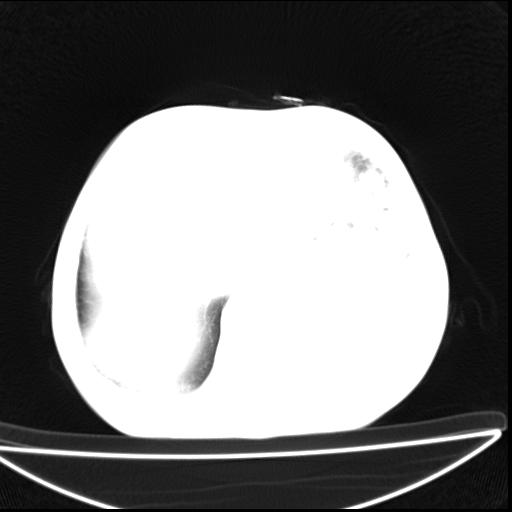

男  70岁,发烧咳嗽4天。盗汗,消瘦。无痰中带血丝,以前有肺tb病史,ct见,双肺tb,左侧胸廓塌陷,左胸膜肥厚粘连。纵隔移位,右侧胸腔积液,大家说说那个心影前左肺舌叶除了肺大炮还有炎症还是干酪性肺炎?有占位吗?我看纵隔淋巴结也大。

是胃,纵膈未见明显肿大淋巴结。

1)两肺继发性肺结核并左肺上叶肺不张,支气管扩张。2)双侧胸膜炎(胸膜增厚+少量胸腔积液)。